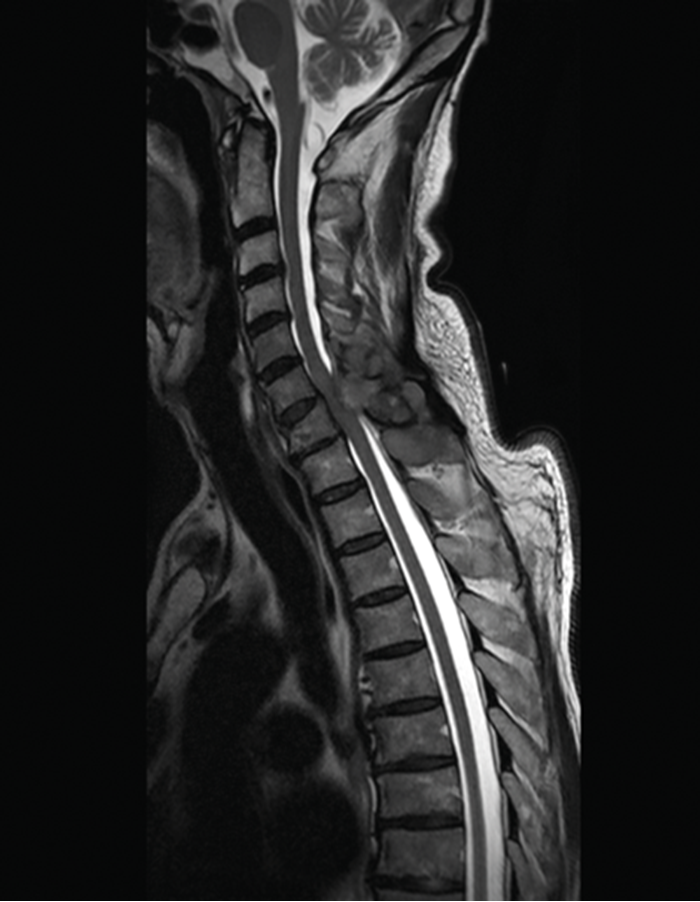

The most frequent pathology when an spine mri is requested si discal hernia (lombosciatic, disc protrusion). Gadolinium is less likely to cause an allergic. An mri (magnetic resonance imaging) scan is an advanced, noninvasive diagnostic tool and imaging technique.

Any irregularities on the spinal cord and other veins surrounding the spine will definitely show up in an mri scan. Side effects of an mri are claustrophobia and anxiety. Magnetic resonance imaging (mri) of the lumbar spine is a safe and painless test that uses a magnetic field and radio waves to produce detailed pictures of the this helps to pinpoint problems in the lumbar spine when the scan focuses on that area. For example, mri of the spine will help assess his condition as a whole, or in certain areas: